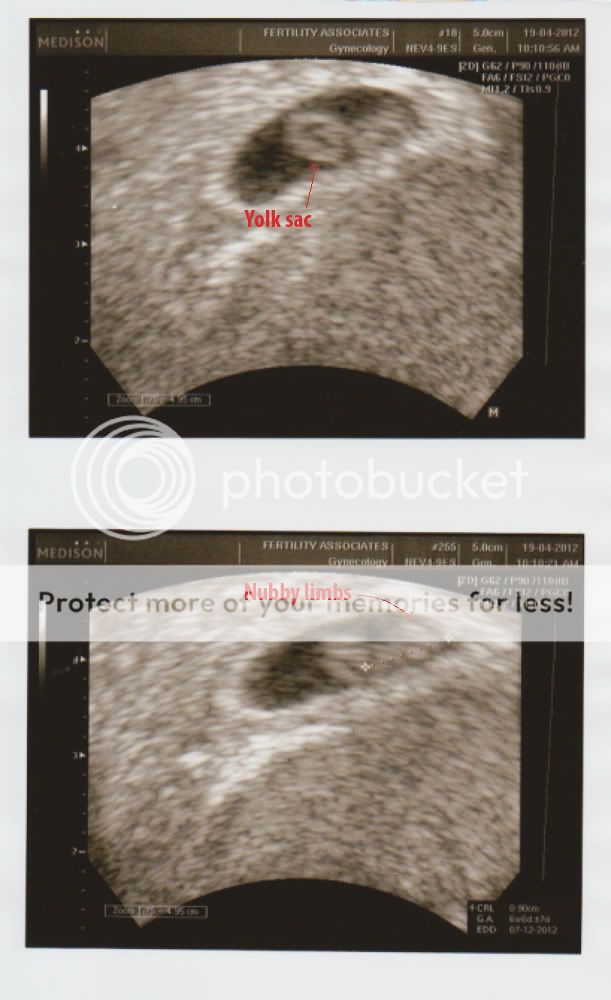

Anywhoo - Here's baby Niv::

AWWW iddy biddy baby!! So its doin well and stuff. How many weeks/months??

Each Friday, is baby's goal day where it ages a week

So tomorrow is week seven... I'm surprised Hercules has made it this far!

Not really that far along, still got ages to go until the first tri is over

Aww, look at the little baby! That is enough to brighten up a crummy day, I think. xD

much luck with baby♥, Nivvy!

Omgosh!

Tiny baby!! >w<